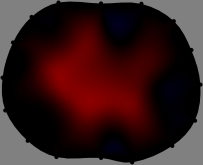

We applied the FER method to experimental data to show its performance. We acquired the boundary geometry and electrode positions as accurate as possible to reduce forward modeling uncertainties[33]. A handheld 3D scanner was used to capture the boundary shape of the thorax and electrode positions (Fig. 1). Then, we set the electrode plane as the horizontal cross-section of the 3D-scanned thorax containing the attached electrodes (Fig. 1). The finite element method was employed to compute the sensitivity matrix 𝕊𝕊\mathbb{S} by discretizing the imaging slice. Here, we used a mesh with 12,001 nodes and 23,320 triangular elements for subject A and a different mesh with 13,146 nodes and 25,610 triangular elements for subject B.

Figs. 3 and 4 compare the performance of the proposed FER method in (20) with the standard regularized least-squares method ((19) when \mathcal{R} is the identity matrix). The regularization parameter of the standard method was heuristically chosen for its best performance, and the parameter of the FER method was set to be one of three different values λ=0.05,0.2,𝜆0.050.2\lambda=0.05,0.2,\infty. The injection current was 1 mARMSRMS{}_{\tiny{\mbox{RMS}}} at 100 kHz, and the frame rate was 9 frames per second. The reference frame at t0subscript𝑡0t_{0} was obtained from the maximum expiration state. The measured data, 𝐕˙(tm)˙𝐕subscript𝑡𝑚\dot{\mathbf{V}}(t_{m}), represent the voltage differences between each time tmsubscript𝑡𝑚t_{m} and t0subscript𝑡0t_{0}. The blue regions, which denote where conductivity decreased by inhaled air, increased during inspiration and decreased during expiration. The FER method with λ=𝜆\lambda=\infty was clearly more robust than the standard method that produced more artifacts originated from the inversion process.

Figure 3: The reconstructed images of the conductivity change of the subject A by the standard regularized least square method and the proposed fidelity-embedded regularization (FER) method for three difference values λ=0.05,0.2,𝜆0.050.2\lambda=0.05,0.2,\infty. Here, the time step is 0.22 seconds (tm+2tm0.22subscript𝑡𝑚2subscript𝑡𝑚0.22t_{m+2}-t_{m}\approx 0.22).